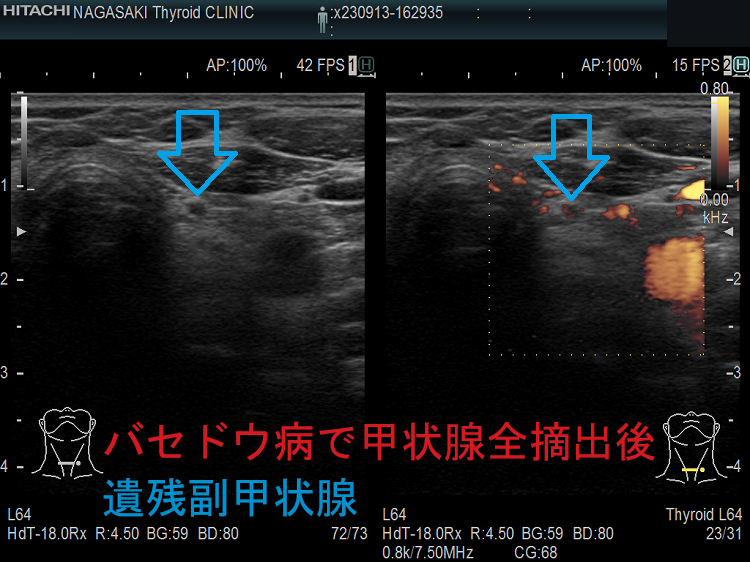

- 甲状腺摘術後、TSH 抑制療法;バセドウ病/甲状腺腫瘍で甲状腺切除と同時に副甲状腺も取ってしまった場合、取らずに温存した場合でも副甲状腺への血管を傷つけた場合

- 甲状腺全摘術時、副甲状腺も1-4腺を同時切除、あるいは切除しなくても栄養血管を損傷

- 甲状腺亜全摘術時、副甲状腺を数腺温存したつもりが、栄養血管を損傷

- 術後副甲状腺機能低下症による低カルシウム血症;術直後のみならず、10年~30年以上して著明な低カルシウム血症で発症する事もある(日腎会誌 2012;54(1):40-47.)(J Clin Diagn Res. 2017 Feb; 11(2): OD07–OD09.)。

ケース①

ケース②